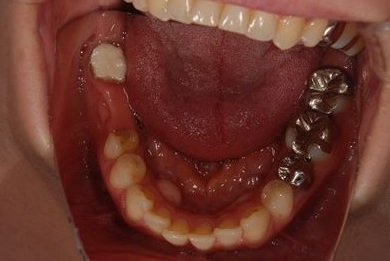

治療前

• 治療前